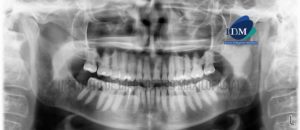

Paciente masculino de 42 años de edad es referido al Instituto de Diagnóstico Maxilofacial (IDM) para evaluación general. En la reconstrucción panorámica (Figura 1)se observa